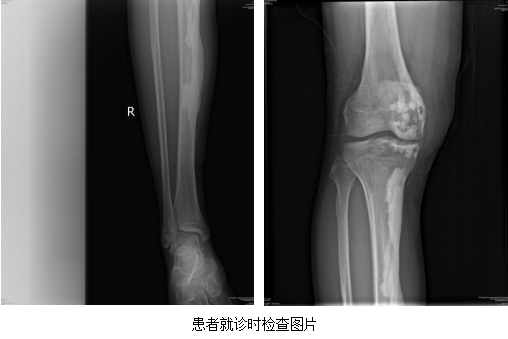

近期,九江市风湿病医院风湿骨关节科接诊了一位来自湖北省的32岁青年男性,夏某。该患者因反复右膝关节肿痛2年,加重3天来我院就诊。当时患者右膝关节轻度肿胀,活动后疼痛明显,休息减轻。曾在当地多家医院就诊,未明确其关节疼痛原因,后到我院风湿骨关节科就诊。鉴于患者右膝关节肿胀疼痛原因不明显,入院后风湿骨关节科医师对患者进行全面检查,发现其风湿检查指标均正常。但是其膝关节MRI和膝关节X线提示其疾病为蜡油样骨病。

蜡油样骨病又称肢骨纹状增生症,是一种极其罕见的骨质硬化性疾病。主要侵犯单侧肢体,双侧侵犯极其少见。增生骨质自上而下沿骨干一侧流注,像蜡烛表面的蜡油样改变。本病由Leri于1928年首次报道,又称Leri病。大多数学者认为该病是因骨膜下毛细血管扩张所致的骨膜发育异常引起。本病发病率男女无差别,多为成年人,病程较长。临床常表现为受累肢体疼痛,活动受限,活动时加剧。X线检查是诊断该病的主要依据,关节多数不受累。